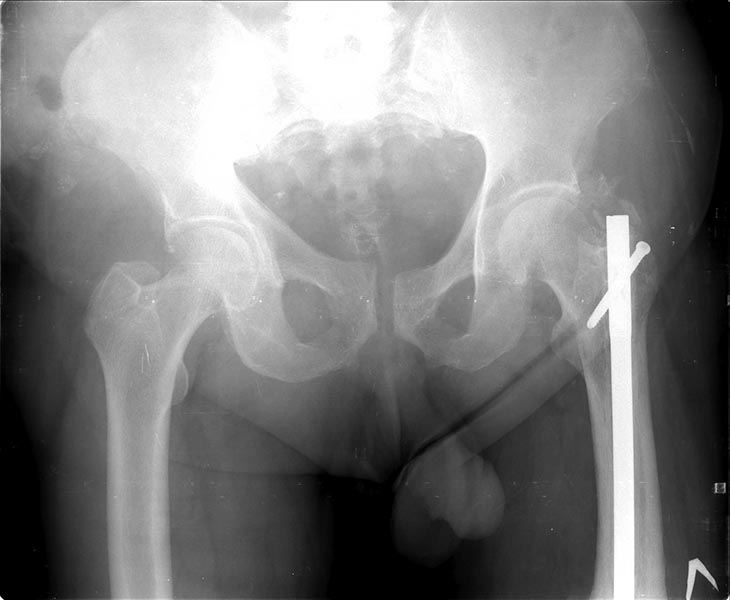

Коротко о пациенте: Возраст 60 лет, мужчина. Со слов травма в 2006 года-ДТП (сбит автомашиной) - в январе 2007 г. выполнено БИОС левого бедра , затем по неизвестным причинам в 2008 году реостеосинтез левого бедра штифтом ( снимков нет). Оперирован в одном из городов Сибири. Передвигался с тростью, с июля 2014 г. был вынужден встать на костыли в связи с усилением болей в области левого коленного сустава, левого бедра. В декабре 2014 г. боли в левом бедре усилились, появилась поталогическая подвижность.Сопутствующие заболевания:

На снимках( это снимки январь 2015г), которые выложил, определяется гипертрофический ложный сустав с/3 бедренной кости, перелом штифта на уровне перелома, штифт канюлированный.Состояние больного удовлетворительное, по анализам компенсирован.